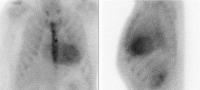

Szintigraphie

Abbildung 3: Technetium-99m-Pyrophosphat-Szintigraphie in anteriorer (links) und lateraler Ansicht (rechts). Visuell deutlich erhöhter Tracer-Uptake im Myokard, verglichen mit dem kontralateralen Thorax (Perugini-Score 3). Nebenbefundlich signifikant gesteigerter Tracer-Uptake im gesamten Sternum bei Zustand nach Sterniotomie und biologischem Aortenklappenersatz.

Keywords: KardiologieSzintigraphie